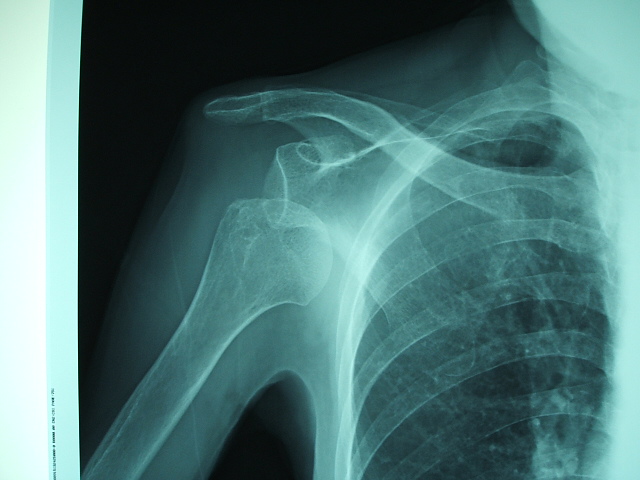

交通事故で肩が突然上がらなくなった場合は、肩関節の脱臼が疑われます。

レントゲンを撮影して、

骨折がなければ、引っ張って整復(もとの位置に戻す)します。

骨折があれば、手術が必要です。